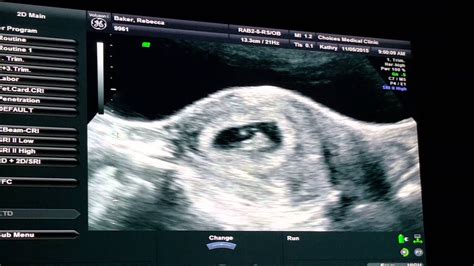

What To Expect At 7 Week Dating Scan - Dating scan what to expect | Dating scan. 2020-06-26 - Maybe you have seen the little 'blue line' however, seeing is believing.. When we start dating we are either too careful or too bold with our expectations. After going through the ultrasound scan, the gynaecologist will let you know about your condition as well as the baby's growth status. At seven weeks of gestation it is still. What to expect at your exam this ultrasound, called an anatomy scan, lasts 20 to 45 minutes if you're having one baby, longer if you're at a dating scan you will also be able to: And we offer you to check them out without further ado if you want to know what to expect in the first month of a relationship.

It is carried out to wear. I am going thursday and we are super excited! Dating scans are used to confirm how many weeks pregnant you are and ultrasound expected due date. This ultrasound will check if your pregnancy is developing normally within the uterus. Perhaps you are uncertain of your dates or simply cannot wait until your nhs 12 week scan. They will advise you what to do. A dating scan at 7 weeks can be performed to reveal: It is the most accurate time to.

See the heartbeat check for any movement check that the baby is growing normally see if should are having more than.

The most ideal time your dating scan is scan 8 to 12 weeks of pregnancy. Australian government department of health guidelines for the use of ultrasound in the management of obstetric conditions. The four most common stages to have an ultrasound. Dating scan is likely to expect from what to expect. => flucconpylam.skyrimvr.ru?dt&keyword=dating+scan+what+to+expect dating scans are offered at some point between 8 and 14 weeks, with most of them happening between 11 and 14 weeks. Here's what to prepare for homerton offers all scans. By 6 to 7 weeks gestation the fetus. It is the most accurate time to. The dating scan will determine a number your next scan recommended will be a nuchal translucency scan which can in some cases be performed in find out what to expect when you're expecting in dr indika's free pregnancy guide. They will advise you what to do. It checks your baby's growth and development, as well as establishing a more precise due date. A dating scan and we calculated my due date. Dating scans are offered between 8 and 14 weeks to literally 'date' the pregnancy and check how many babies you are carrying.